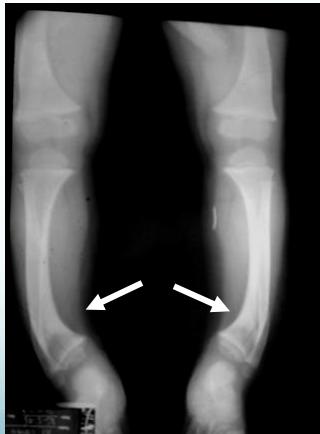

- Rickets

Rickets

Rickets - Improves with time

Indications: X-ray when severe or possibly pathologic

Recommended Views:

- Standing AP film: Long film (hips to ankles) with patellae directed forwards

Radiological Parameters to Assess:

- Medial Physeal Slope

- Femoral-Tibial Axis